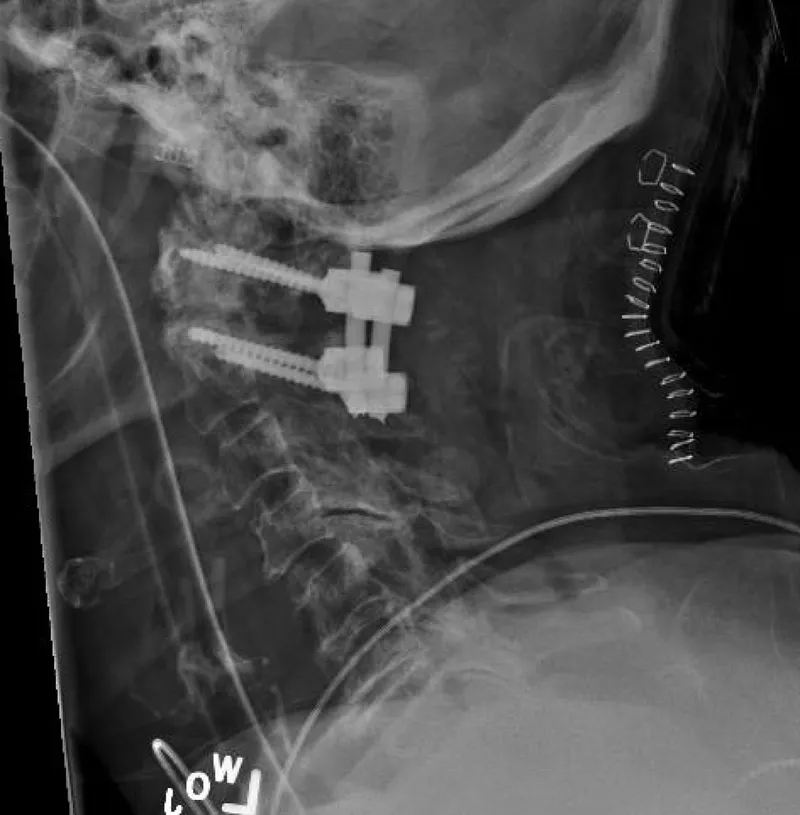

- Hardware Failure: Screw malposition, breakage, cage migration.

- X-ray (AP/Lateral/Flexion-Extension): Initial check for alignment, hardware integrity, and instability.

- CT Scan: 🥇 Gold standard for evaluating bony fusion (arthrodesis). Best modality to visualize pseudarthrosis (failed fusion).

- MRI: Assesses soft tissues. Indicated for new/worsening neurologic deficits to rule out hematoma, abscess, or persistent nerve compression.